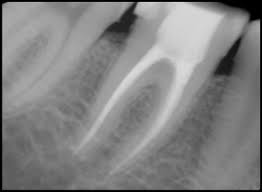

Лечението на двете заболявания е сходно,и цели премахването на инфектираната тъкан от зъбът и почистването на корено-каналната система на зъба с помощта на различни разтвори и медикаменти.След това корена на зъба се запълва с биосъвместим материал и се затваря херметически за да не се развира реинфекция.